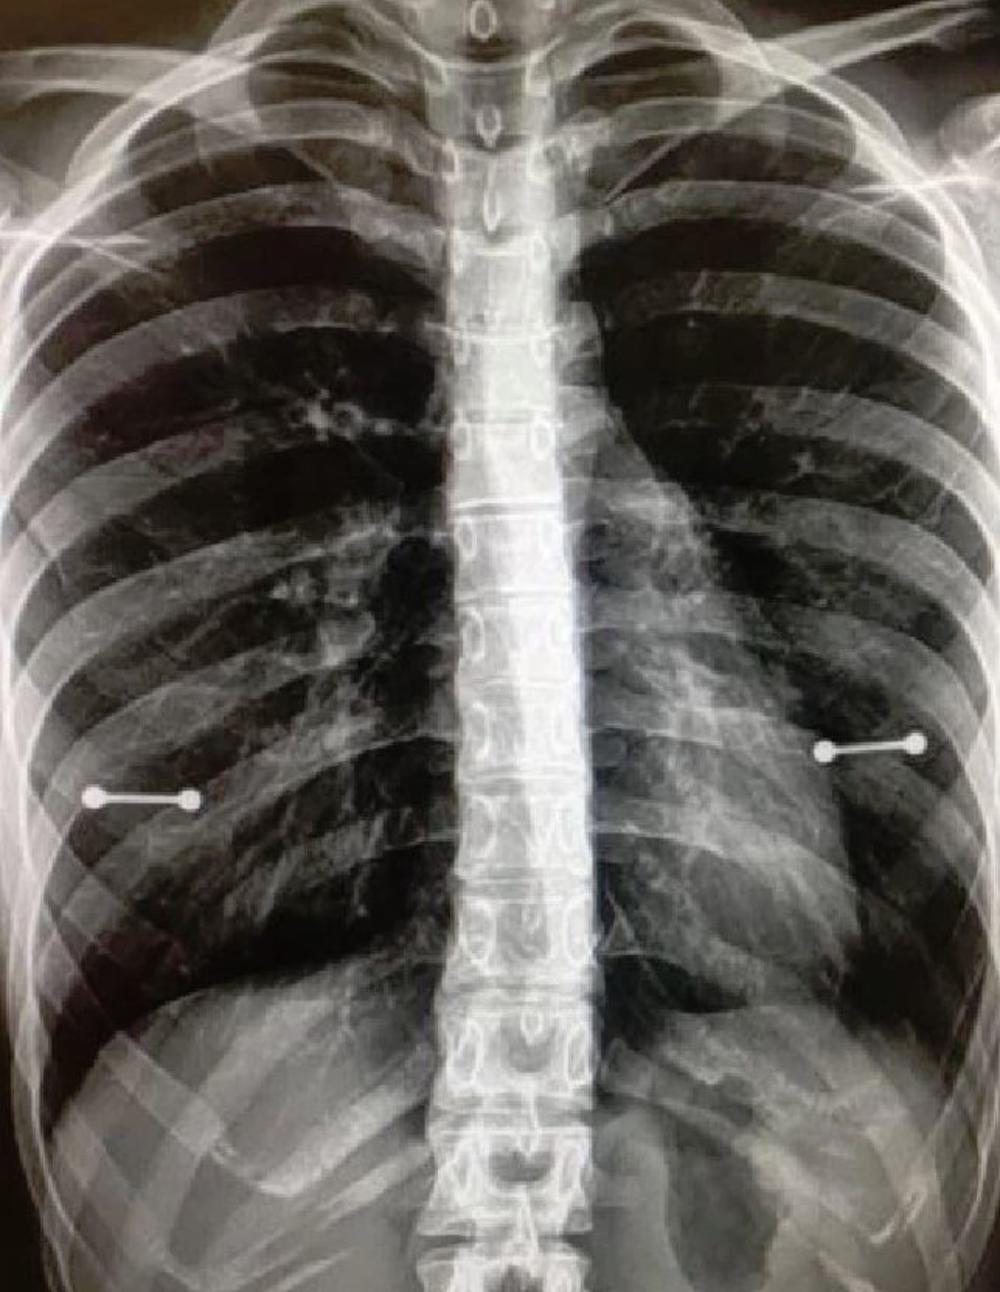

Sidni Alen iz Klirvotera u Floridi bradavice je probušila u junu, što joj je bio rođendanski poklon od sestre.

Ali na njenu žalost to se promenilo kad je prošle nedelje išla na rutinski rendgenski pregled, a sa sobom je povela majku.

Sidni pati od siringomijelije - retkog stanja koje može deo leđne moždine napuniti tečnošću - zbog čega redovno ide na preglede. Ali sad je bila prvi put otkako je probušila bradavice, a ono što nije znala je da se na rendgenu vidi metal.

- Mama mi je danas saznala da imam probušene bradavice - napisala je na Tviteru, ali objavu koja je postala viralna je obrisala.